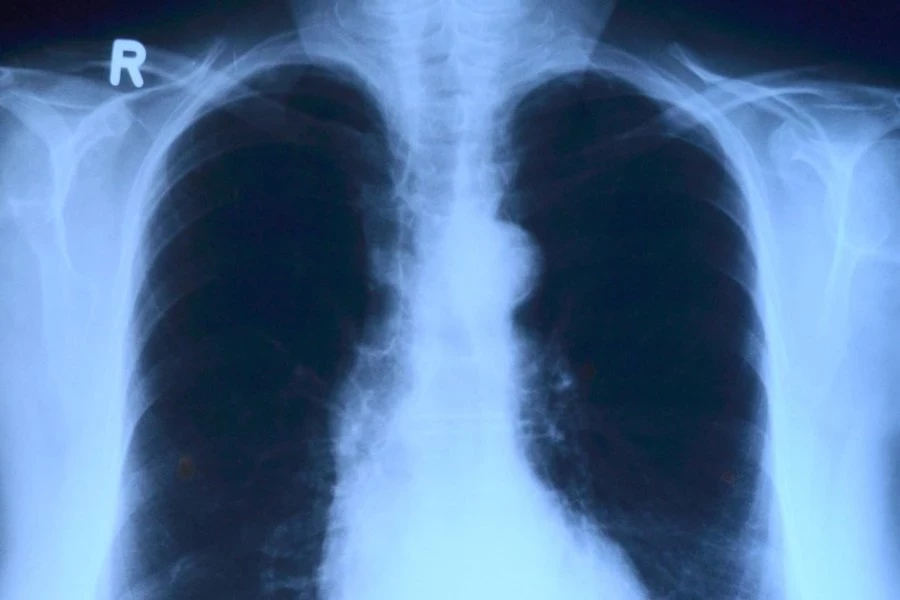

Учёные НИТУ МИСиС и Национального медицинского исследовательского центра онкологии разработали новый препарат, который может помочь в лечении рака. Он основан на использовании особых бактерий, которые получают энергию от солнечного света и содержат вещество под названием бактериохлорин, пишут «Известия».

Когда этот препарат вводится в организм больного раком, он сосредотачивается в опухолевых клетках. Затем на эти клетки направляют специальный световой луч. В результате бактериохлорин в опухоли становится активным и уничтожает раковые клетки.

Этот метод лечения называется фотодинамической терапией (ФДТ). Он применяется в случаях, когда другие методы лечения не справляются с особенно стойкими стволовыми раковыми клетками, которые могут вызывать повторное появление рака и образование метастазов.